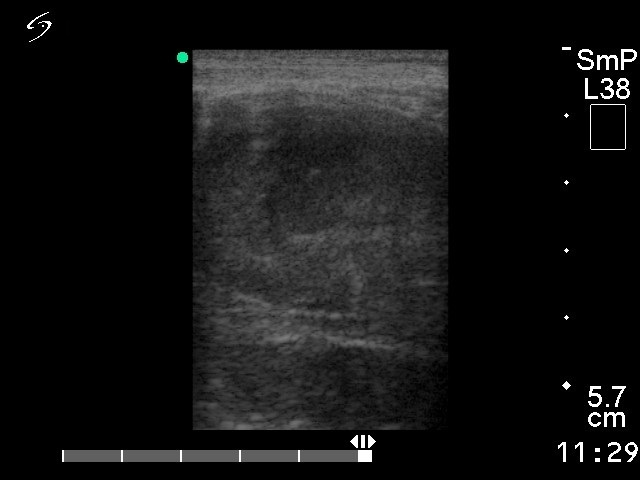

Ultrasonography. The basic echo structure of the thyroid was normal. There were multiple hypoechogenic nodules in the right lobe.